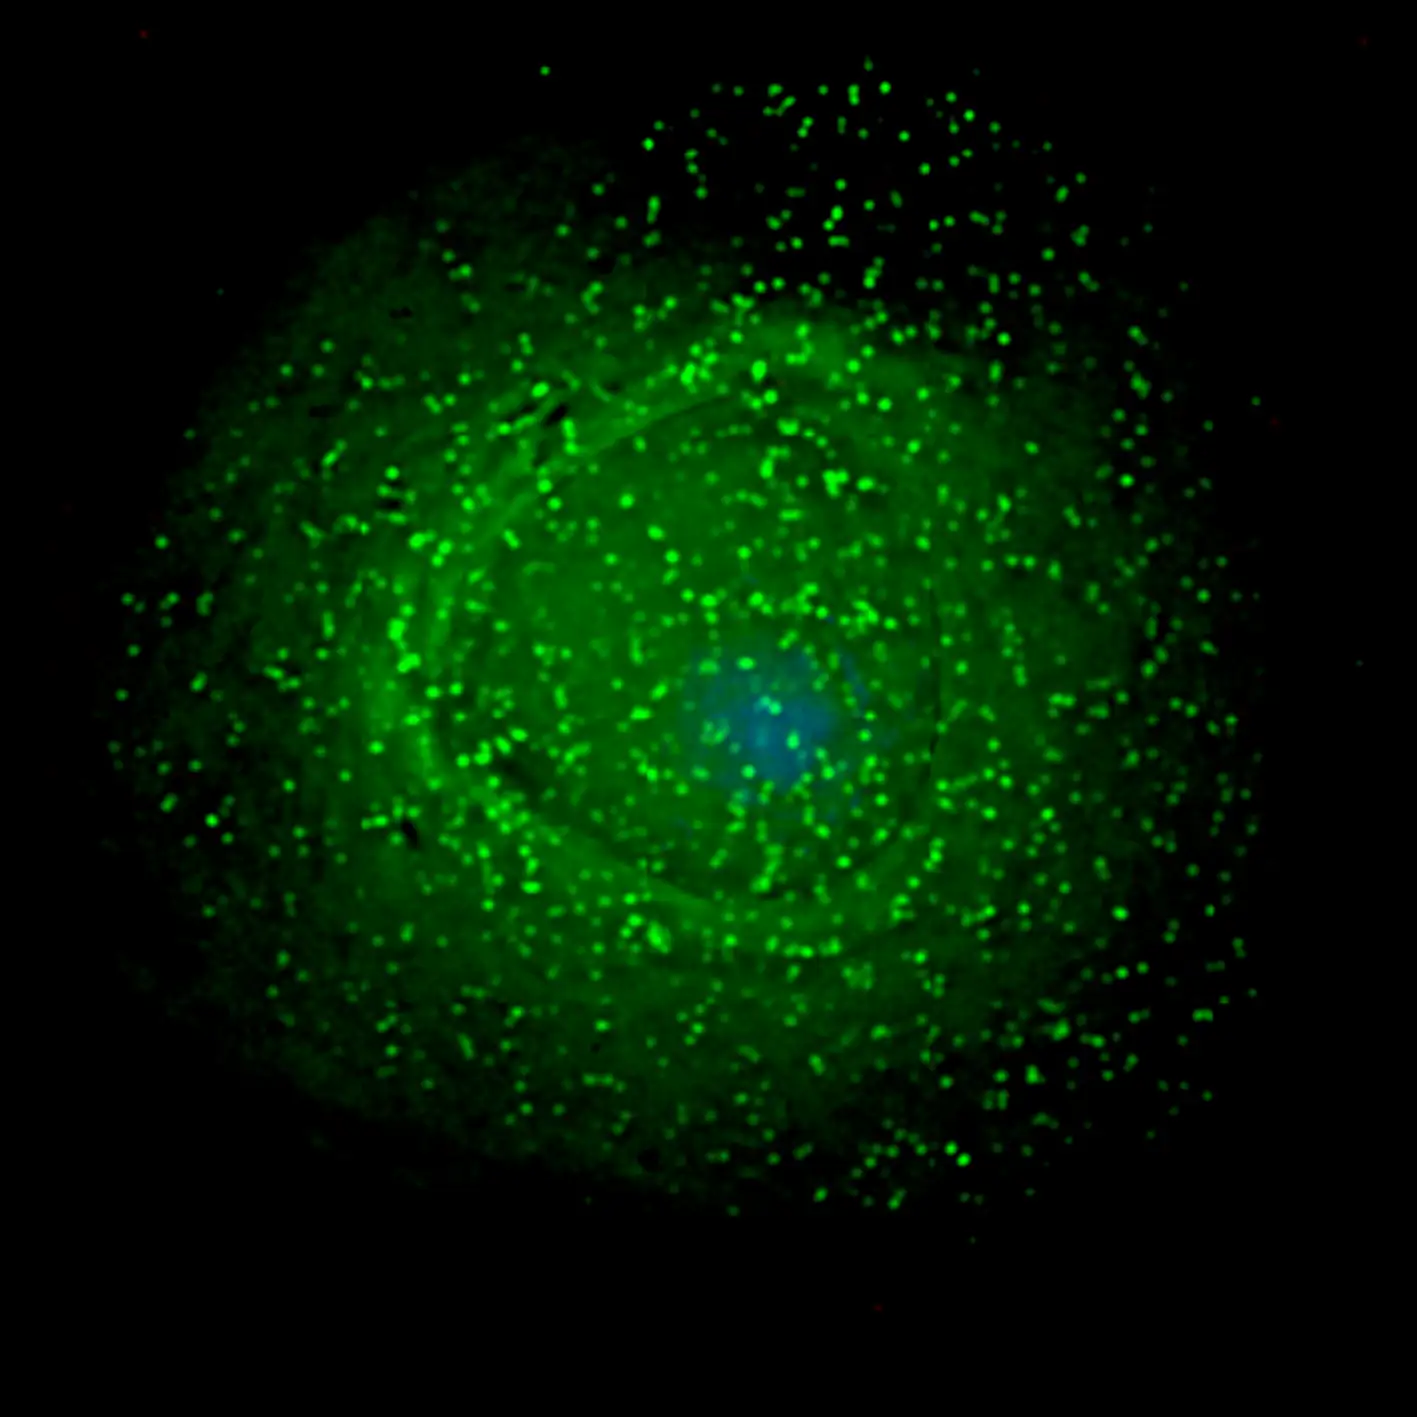

HIV的独特之处在于它攻击的目标。不像大多数病原体直接攻击特定的器官或组织,HIV攻击的是人体的免疫系统本身。它主要靶向一种叫做CD4阳性T细胞的白细胞,这些细胞是免疫系统的指挥中心,负责协调身体对各种感染的防御反应。

当HIV进入人体后,其表面的包膜糖蛋白gp120会与T细胞表面的CD4分子结合。这种结合就像是一把钥匙打开了一扇门。随后,病毒会利用细胞表面的另一种受体——CCR5或CXCR4——完成进入细胞的过程。一旦进入细胞内部,病毒就会脱去外衣,释放出自己的遗传物质,开始它的复制周期。

随着感染的进展,CD4阳性T细胞的数量逐渐下降。正常人的CD4细胞计数在每微升五百到一千五百之间。当这个数字降到两百以下时,患者就开始进入艾滋病阶段。此时,免疫系统已经严重受损,无法抵御那些在健康人体内不会造成问题的机会性感染。卡氏肺孢子虫肺炎、巨细胞病毒感染、卡波西肉瘤、弓形虫病……这些原本罕见的疾病在艾滋病患者身上变得司空见惯。

尽管鸡尾酒疗法取得了巨大的成功,它仍然不是一种治愈方案。患者必须终身服药,一旦停药,病毒就会卷土重来。这是因为HIV有一个叫做病毒储存库的秘密武器。在感染的早期,一些病毒会将自己的基因整合到休眠的免疫细胞中。这些细胞不活跃,因此不会产生新的病毒颗粒,也不会被药物杀死。但它们携带着病毒的遗传蓝图,随时准备在条件成熟时重新激活。